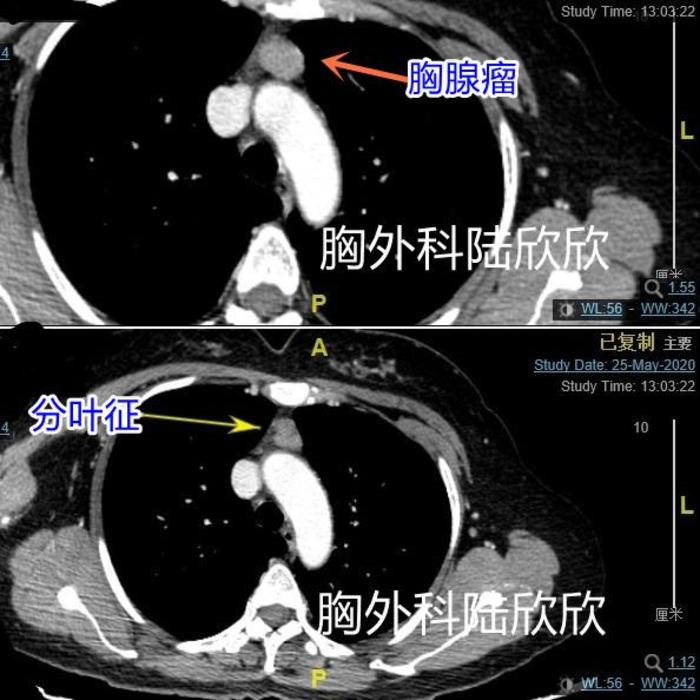

有一个病人术前因咳嗽发现有前纵隔肿瘤,肿瘤偏向左侧。肿瘤不大,最大径25毫米。包膜完整,术前考虑低度恶性的胸腺瘤这么小的肿瘤一般不会咳嗽。咳嗽的原因是着凉后上感引起的咳嗽

上图,CT示胸腺瘤局部稍有分叶征。

术后分析此患者CT,有分叶征,在分叶征附近肿瘤组织的前后密度不同:靠腹侧的密度低一些,看起来暗一些;靠背侧的密度高一些,看起来亮一些。可能这是一个提示恶性度较高的征象。视频如下: